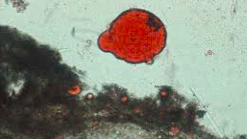

What is the qualitative stool fat assessment?

What might this be?